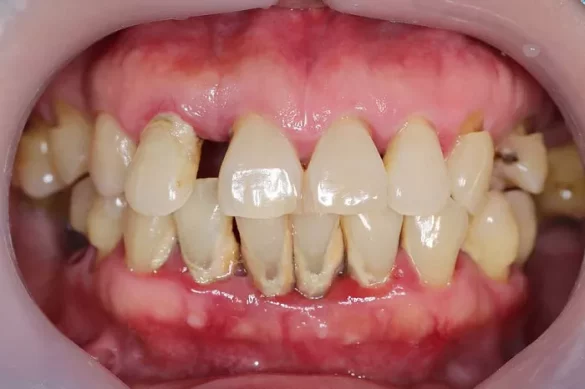

Periodontal disease is primarily caused by the buildup of plaque, a sticky film of bacteria that forms on the teeth. If not removed through regular brushing and flossing, plaque can harden into tartar, which further irritates the gums. Poor oral hygiene habits, smoking, and certain underlying health conditions like diabetes can exacerbate the problem. The disease typically progresses from gingivitis, characterized by red, swollen gums that bleed easily, to periodontitis. In periodontitis, the infection spreads deeper, causing the gums to pull away from the teeth, forming pockets. These pockets can trap more bacteria, leading to further destruction of the periodontal ligament and alveolar bone. For example, a person who smokes and has poor oral hygiene is at a much higher risk of developing severe periodontitis compared to a non-smoker with good oral care practices.

Symptoms of periodontal disease include persistent bad breath, gum recession (where the gums pull back and expose the tooth roots), tooth mobility (looseness of the teeth), and deepening gum pockets. Diagnosis usually involves a comprehensive dental examination, including measurement of gum pocket depth using a periodontal probe and X-rays to assess bone loss. A dentist may also look for signs of inflammation, such as redness and swelling of the gums. For instance, if a patient complains of bleeding gums and a bad taste in the mouth, the dentist will perform a series of tests to determine if it is due to periodontal disease and how advanced it is.